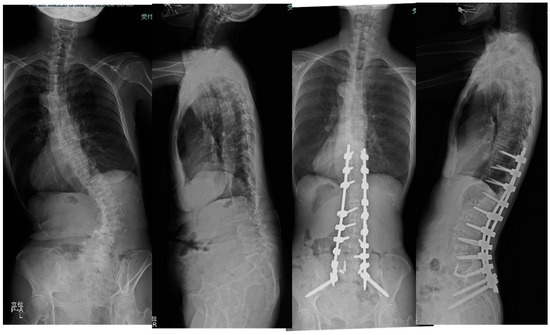

Clinical and Radiologic Analysis of Minimally Invasive Anterior–Posterior Combined Surgery for Adult Spinal Deformity: Comparison of Oblique Lateral Interbody Fusion at L5/S1 (OLIF51) versus Transforaminal Interbody Fusion

by Yoshihisa Kotani, Atsushi Ikeura, Takahiro Tanaka and Takanori Saito

Medicina 2024, 60(1), 107; https://doi.org/10.3390/medicina60010107 - 6 Jan 2024

Background and Objectives: Although adult spinal deformity (ASD) surgery brought about improvement in the quality of life of patients, it is accompanied by high invasiveness and several complications. Specifically, mechanical complications of rod fracture, instrumentation failures, and pseudarthrosis are still unsolved issues. To [...] Read more.

Background and Objectives: Although adult spinal deformity (ASD) surgery brought about improvement in the quality of life of patients, it is accompanied by high invasiveness and several complications. Specifically, mechanical complications of rod fracture, instrumentation failures, and pseudarthrosis are still unsolved issues. To better improve these problems, oblique lateral interbody fusion at L5/S1 (OLIF51) was introduced in 2015 at my institution. The objective of this study was to compare the clinical and radiologic outcomes of anterior–posterior combined surgery for ASD between the use of OLIF51 and transforaminal interbody fusion (TLIF) at L5/S1. Materials and Methods: A total of 117 ASD patients received anterior–posterior correction surgeries either with the use of OLIF51 (35 patients) or L5/S1 TLIF (82 patients). In both groups, L1–5 OLIF and minimally invasive posterior procedures of hybrid or circumferential MIS were employed. The sagittal and coronal spinal alignment and spino-pelvic parameters were recorded preoperatively and at follow-up. The quality-of-life parameters and visual analogue scale were evaluated, as well as surgical complications at follow-up. Results: The average follow-up period was thirty months (13–84). The number of average fused segments was eight (4–12). The operation time and estimated blood loss were significantly lower in OLIF51 than in TLIF. The PI-LL mismatch, LLL, L5/S1 segmental lordosis, and L5 coronal tilt were significantly better in OLIF51 than TLIF. The complication rate was statistically equivalent between the two groups. Conclusions: The introduction of OLIF51 for adult spine deformity surgery led to a decrease in operation time and estimated blood loss, as well as improvement in sagittal and coronal correction compared to TLIF. The circumferential MIS correction and fusion with OLIF51 serve as an effective surgical modality which can be applied to many cases of adult spinal deformity. Full article

Show Figures

Figure 1